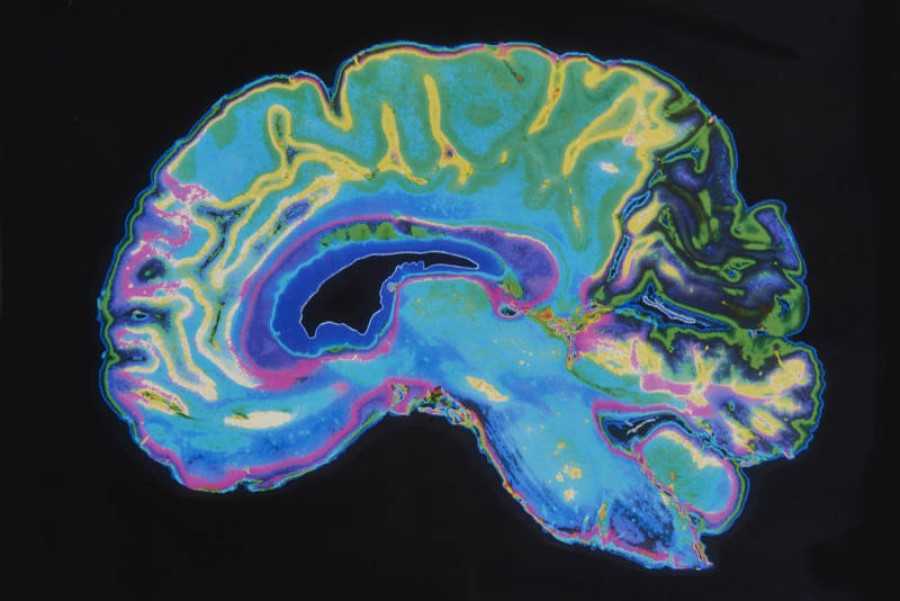

Estudios recientes han demostrado que estos estímulos y la forma de relacionarnos con los videojuegos pueden llegar a modificar las estructuras del cerebro de forma medible. Es decir, tienen un efecto sobre nuestro cuerpo. Por ello, neurocientíficos y psicólogos están trabajando para encontrar el significado clínico de estos cambios. En la actualidad, existe un consenso sobre que los videojuegos pueden ser mayoritariamente beneficiosos para el cerebro, aunque vale la pena matizar esta frase debido a las muchas variables que hay que estudiar por separado.

Estos cambios los pudieron observar en un estudio llevado a cabo por la Universidad de Szeged, en Hungría, donde demostraron que la parte derecha delhipocampo aumentaba de volumen tras jugar dos meses a videojuegos de plataformas 3D. El hipocampo es la región cerebral encargada del aprendizaje y la memoria, por lo que un crecimiento podría tener consecuencias positivas en la vida diaria. Durante el estudio también se observó crecimiento en las áreas prefrontales, que están relacionadas con la planificación de comportamientos complejos, en la personalidad y en la toma de decisiones.

En otro tipo de videojuegos, como los de acción, es algo más complejo. Según se ha observado, los efectos en el cerebro son distintos según la estrategia que emplea el usuario para navegar por el mapa. Por ello, tras meses jugando a videojuegos, los investigadores encontraron resultados mixtos. En algunos casos identificaron un aumento en el hipocampo similar a los juegos de plataformas, pero en otras, una disminución. Ahora bien, no todos los efectos se reflejan en cambios de las estructuras cerebrales. Otro estudio de la Universidad de Montreal, Canadá, con el mismo tipo de videojuegos se centró en observar otras capacidades cognitivas. Tras analizar los resultados encontraron que los videojuegos de acción tenían un impacto positivo en la atención, el aprendizaje, la percepción espacial y la velocidad de procesamiento de sus jugadores.